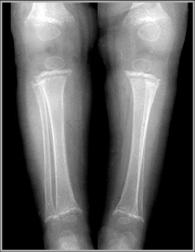

Scurvy